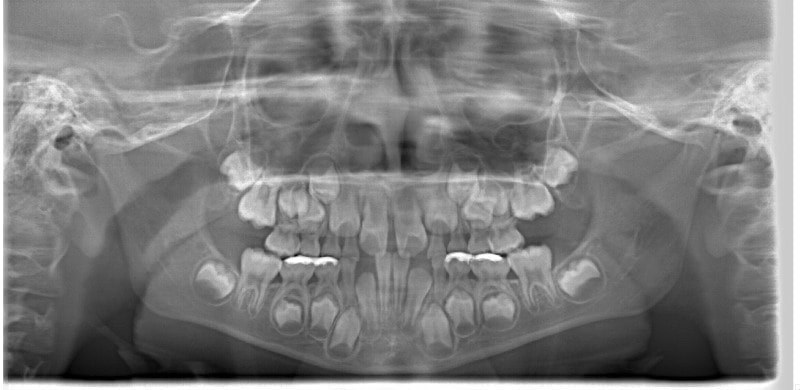

準備矯正終了時レントゲン分析

フェイスマスクによる上顎の前方牽引の効果が認めらます。

歯胚の位置は大きな問題はありません。

上顎劣成長の場合、統計的に左上犬歯のスペースに注意する必要があります。

手根骨の骨年齢は実年齢よりも低く男児なので、今後旺盛な下顎の成長が予測されます。